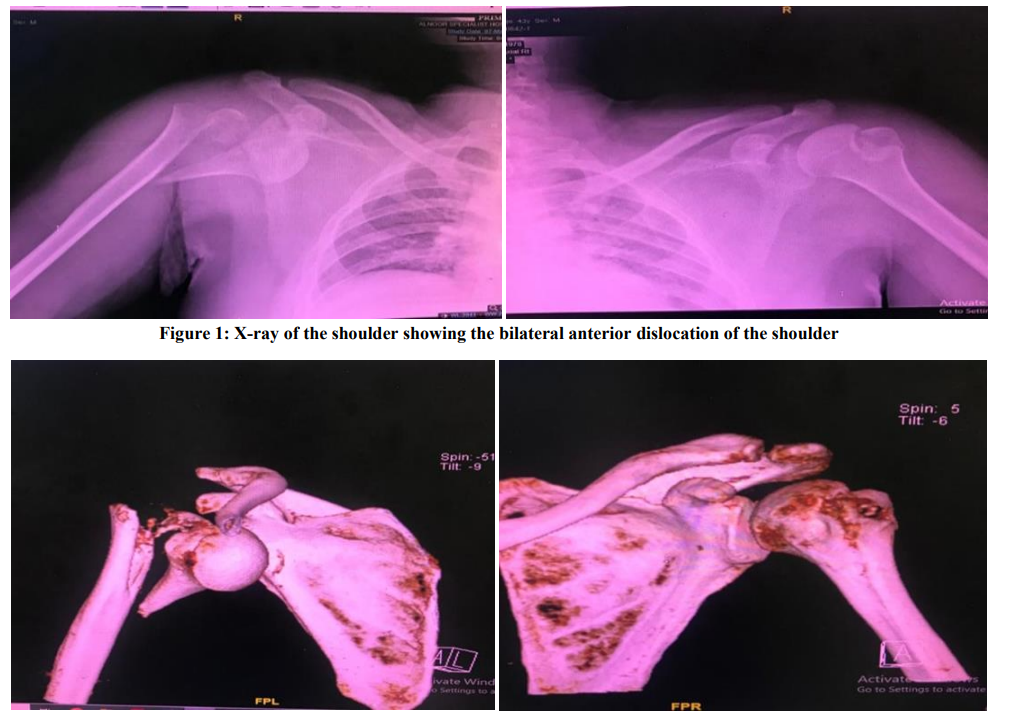

Bilateral Shoulder Anterior Dislocation with Proximal Humerus Fracture After Seizure Attack Post Covid-19 Vaccine

Abdullah Alrowithi, Abdullah Abdulrahman Marzogi, Salman Salem Alsharif

International Journal of Innovative Research in Medical Science·September 10, 2022